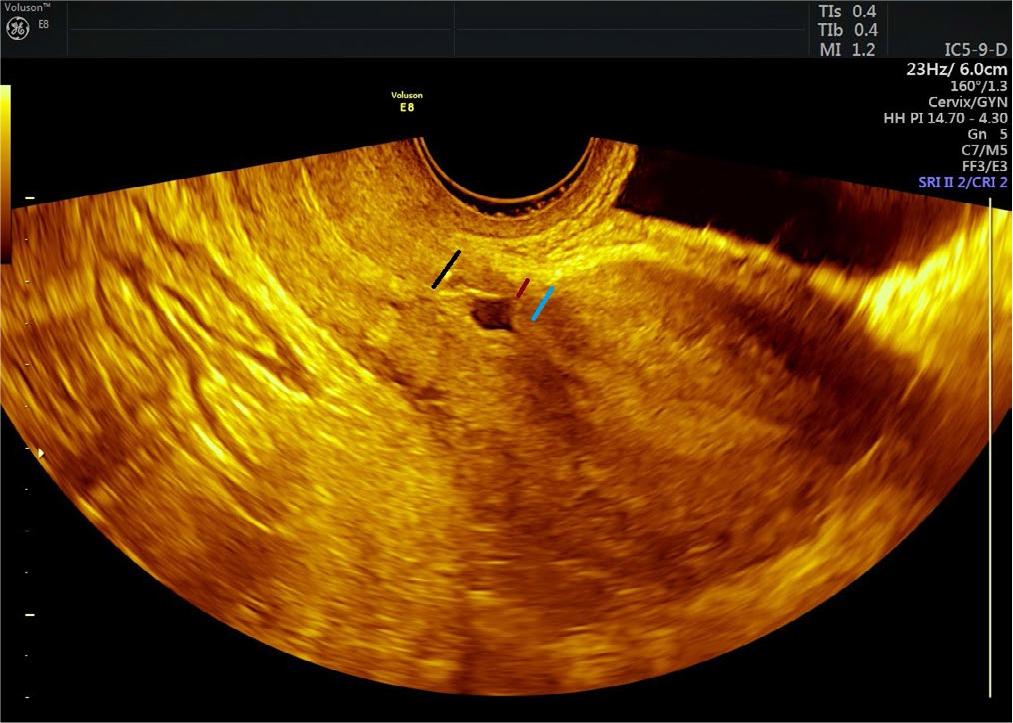

Fig. 1.